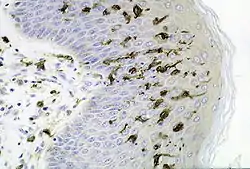

Dendritic cells in skin